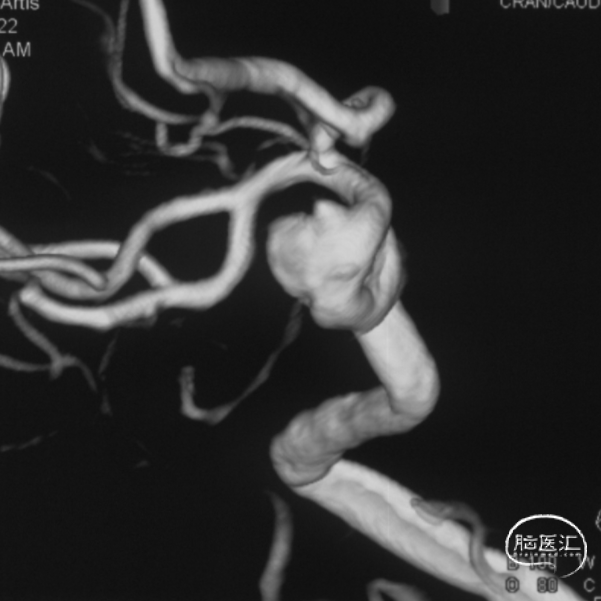

术前影像学资料

外院DSA

右侧颈内动脉眼动脉段-海绵窦段串联两枚动脉瘤,分别大小约:

① 8.8mm*5.9mm*5.2mm,瘤颈宽7.0mm;

② 6.8mm*4.3mm*3.6mm,瘤颈宽3.3mm。

治疗过程

支架导管及弹簧圈微导管先后超选到位,其中弹簧圈微导管超选入远端眼动脉段动脉瘤内备用,根据测量结果,选用YonFlow®血流导向密网支架 4.5mm/30mm、弹簧圈9mm/40cm,先部分推出弹簧圈在动脉瘤内提供保护。再释放密网支架。